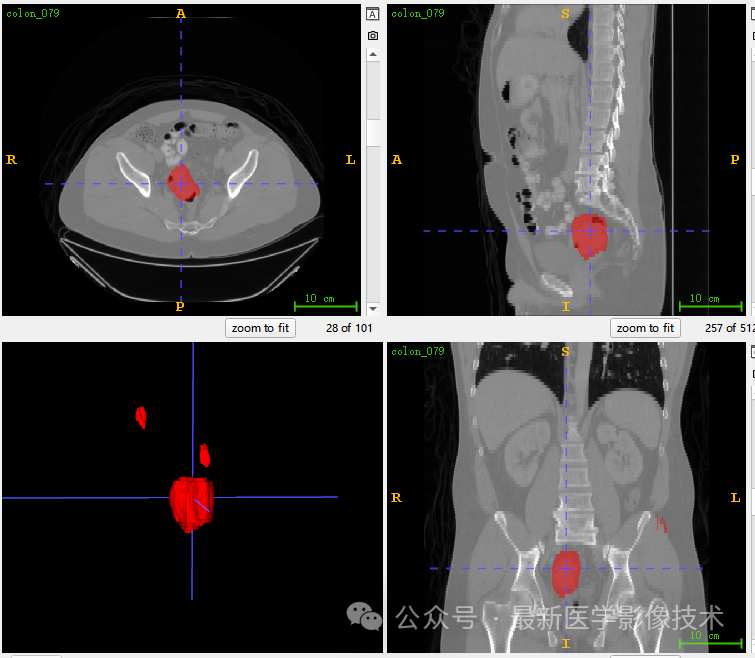

5、验证集分割结果

左图是金标准结果,右图是预测结果。